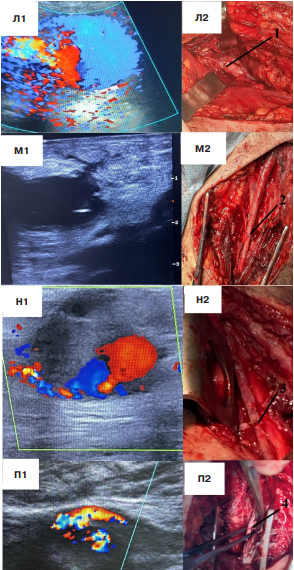

Оперативное лечение псевдоаневризмы поверхностной бедренной артерии, задней большеберцовой артерии, лучевой артерии

Мы решили объединить эти локализации в одну группу ввиду выбора единой хирургической тактики. Перечисленные артерии достаточно длинные, их повреждения находятся не вблизи бифуркаций, что позволяет после удаления псевдоаневризмы восстановить артерию анастомозом "конец-в-конец" с применением полипропиленовой нити 6/0 (рис. 7).

Следует учесть, что единственная псевдоаневризма лучевой артерии являлась наименьшей во всей выборке и составляла 2 см в диаметре. По данным УЗИ определялся дефект стенки артерии, при этом сама полость аневризмы практически полностью тромбирована (рис. 8).

В данной ситуации показанием для оперативного лечения стала нейропатия лучевого нерва, возникшая в результате сдавления. Псевдоаневризма удалена, полипропиленовой нитью 7/0 выполнен анастомоз лучевой артерии по типу "конец-в-конец" (рис. 8). Послеоперационный период протекал без особенностей. Симптомы нейропатии регрессировали на 20 сут. после вмешательства.

Рис. 7. Оперативное лечение псевдоаневризмы поверхностной бедренной артерии, задней большеберцовой артерии.

Примечание: Л1, М1 — УЗИ пациентов с псевдоаневризмой поверхностной бедренной артерии; Л2, М2 — поверхностная бедренная артерия после реконструкции "конец-в-конец"; Н1, П1 — УЗИ пациентов с псевдоаневризмой задней большеберцовой артерии; Н2, П2 — задняя большеберцовая артерия после реконструкции "конец-в-конец". 1 — анастомоз поверхностной бедренной артерии "конец-в-конец"; 2 — анастомоз поверхностной бедренной артерии "конец-в-конец"; 3 — анастомоз задней большеберцовой артерии "конец-в-конец"; 4 — анастомоз задней большеберцовой артерии "конец-в-конец".

Рис. 8. Оперативное лечение псевдоаневризмы лучевой артерии.

Примечание: Р1 — ультразвуковой снимок псевдоаневризмы; Р2 — псевдоаневризма лучевой артерии после выделения; Р3 — реконструкция лучевой артерии анастомозом "конец-в-конец".